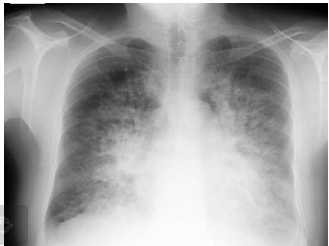

Paciente de 66 anos, do sexo masculino, com antecedente de hipertensão, dá entrada no Pronto Socorro com quadro de dispneia de instalação em horas, após comparecer a churrasco.

Admitido prontamente na UTI, apresenta os seguintes sinais vitais: FC 120, PA 210x120, FR 46, SatO2 90% em máscara de O2. Apresenta, ainda, a seguinte radiografia de tórax:

O paciente foi intubado, iniciada ventilação mecânica invasiva com os seguintes parâmetros em pressão controlada: PEEP 10, PC 15, FR 25, FiO2 100%. Coletada gasometria arterial com o seguinte resultado: pH 7,4, pCO2 40, HCO3 24, pO2 105, SatO2 98%. Tendo em vista os critérios de Berlin para diagnóstico de Síndrome do Desconforto Respiratório do Adulto, esse paciente não se encaixa no seguinte critério: